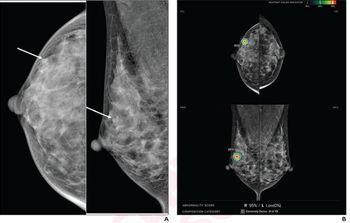

[[{"type":"media","view_mode":"media_crop","fid":"11554","attributes":{"alt":"Stephen Rose","class":"media-image media-image-left","id":"media_crop_8501769795264","media_crop_h":"0","media_crop_image_style":"-1","media_crop_instance":"218","media_crop_rotate":"0","media_crop_scale_h":"0","media_crop_scale_w":"0","media_crop_w":"0","media_crop_x":"0","media_crop_y":"0","style":"margin: 5px; float: left;","title":" ","typeof":"foaf:Image"}}]]In February 2011, the FDA approved the first X-ray mammography system that provides 3-D images for breast cancer screening and diagnosis,

In this podcast, Stephen Rose, MD, president and CEO of Houston Breast Imaging and a principal investigator of the 3-D tomosynthesis clinical trials in 2010, discusses the benefits of the new technology and what his practice learned when implementing the screening program. .